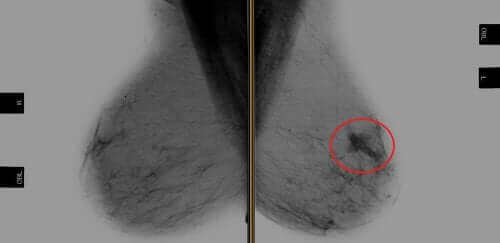

Trastuzumab, HER2 pozitif meme kanseri olan hastalar için onkogene karşı ilk hedefli tedavidir. Onkogen, dokuda kanser oluşumunu indükleyen mutasyon veya transformasyon için yüksek kapasiteye sahip bir gendir.

Aynı zamanda, HER2 pozitif meme kanseri, bu protein için aşırı eksprese edilmiş reseptörlere sahip bir neoplazma tipini ifade eder. HER2 proteinleri, normal durumlarda gerekli olan HER2 geni tarafından üretilen meme hücreleri üzerindeki reseptörlerdir. Bu proteinler meme hücrelerinin bölünmesine ve kendilerini onarmasına izin verir.

HER2 pozitif meme kanserleri, insanlarda meme tümörlerinin %20-30’unu oluşturur. Uzmanlar, bu kanser türünü, düşük nükssüz sağkalım ve genel sağkalım da dahil olmak üzere kötü bir prognozla ilişkilendirdi.